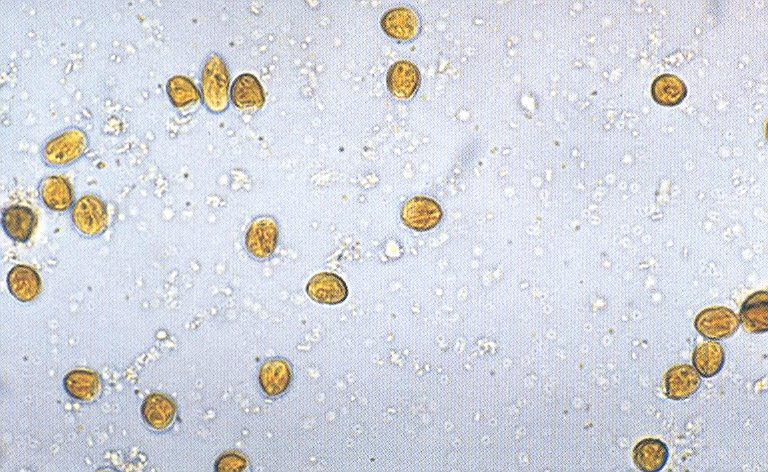

Diagnostiek

Het stellen van een diagnose kan soms net spoorzoeken zijn. Soms is het eenvoudig en soms is het lastig.

Onze diagnostische mogelijkheden hebben we uitgebreid door de aanschaf van vele soorten van apparatuur en het volgen van allerlei cursussen.